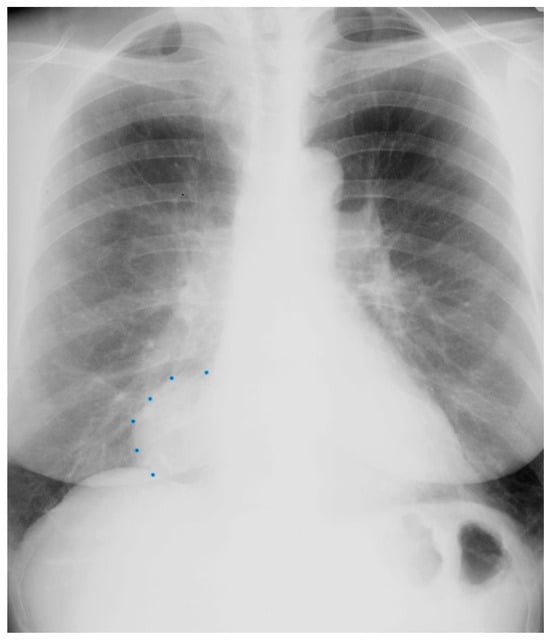

Figure 1.

Posteroanterior chest X-ray in congenital complete absence of the left portion of the parietal pericardium: A 30-year-old female was referred to a cardiologist because of an unusual chest X-ray done as part of an executive physical. She was asymptomatic and her vital signs and heart sounds were normal and there was no heart murmur or arrhythmia. The image is well centered, there is a good inspiration and the C-T ratio is <0.5. The heart is shifted into the left chest and the right heart border is obscured because it overlies the dorsal vertebral bodies. The pulmonary artery segment (outlined with blue dots) is enlarged but the pulmonary vascularity is normal, making left to right shunting unlikely. Echocardiography and Cardiac MRI confirmed she had CCALPPP. She was reassured. No treatment was necessary.